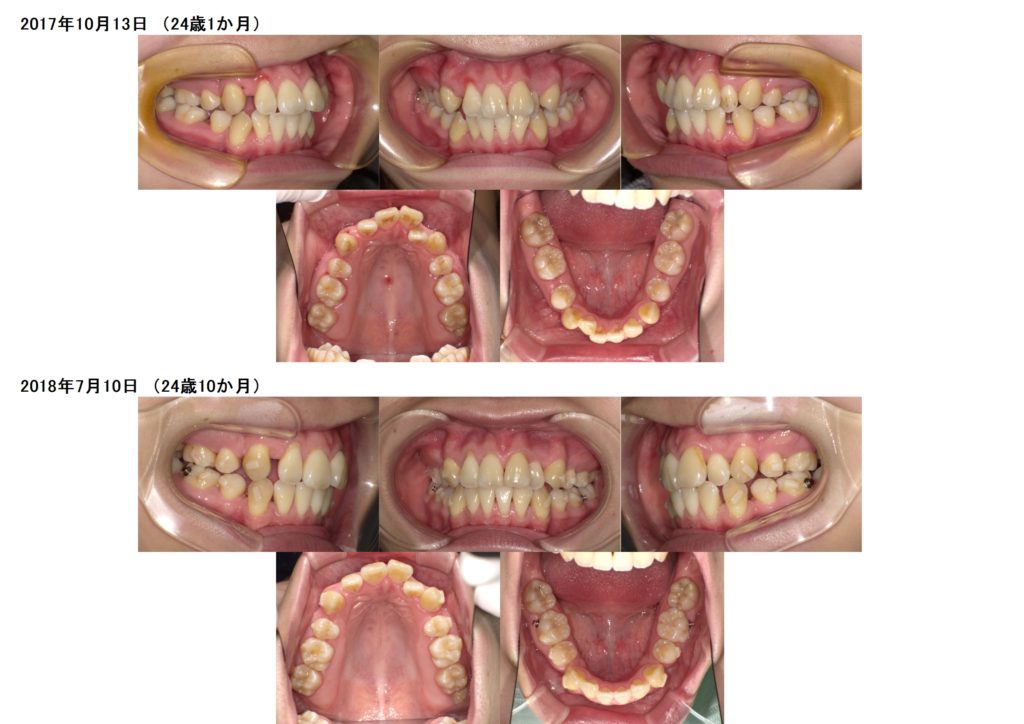

↑治療前、治療後の口腔内写真の比較です。

上下の顎のアーチを整えながら、抜歯した隙間を利用し噛み合わせの深さや突出している部分も改善しているのが分かると思います。

約2年間のブラケット治療になりますが、お口の中もとても変化します。突出している方だと横顔のラインも変わりますので、